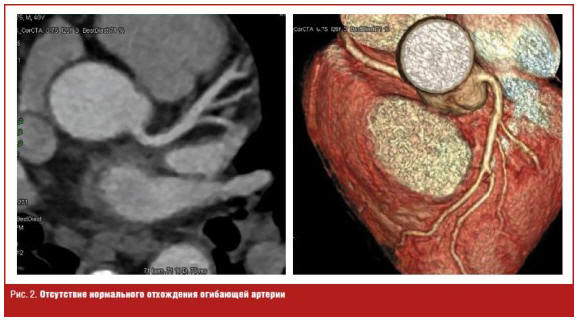

При проведении МСКТ-коронароангиографии у 9 (29,0%) из 31 пациента с

дисплазией соединительной ткани диагностированы структурные изменения коронарных

сосудов (рис. 1): у одного пациента (3,2%) — аномалия отхождения артерий

(отсутствие нормального отхождения огибающей артерии) (рис. 2, 3), у 4 (12,9%) —

гипоплазия коронарных артерий (рис. 4), у 4 (12,9%) — аномалии расположения

коронарных артерий с наличием «мышечных мостиков» (рис. 5).